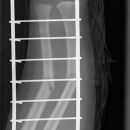

Unterarmschaft Fraktur

Monteggia-Fraktur

Galeazzi-Fraktur